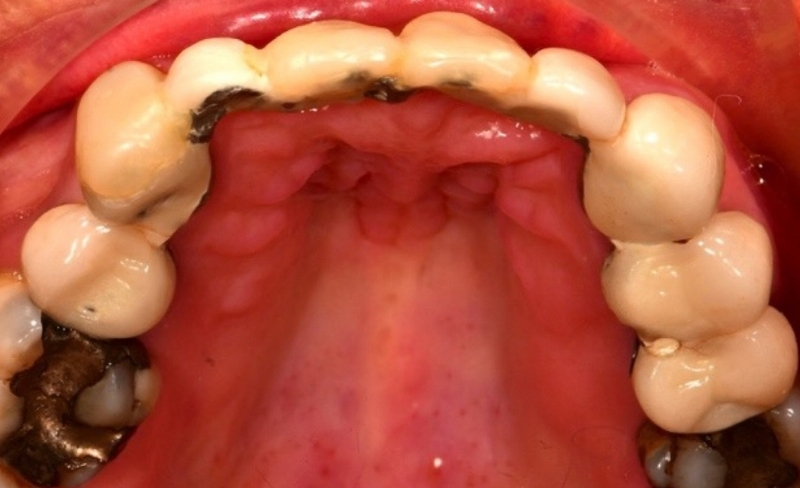

Smile makeover to manage the failing upper bridge using crowns, bridges and dental implants.